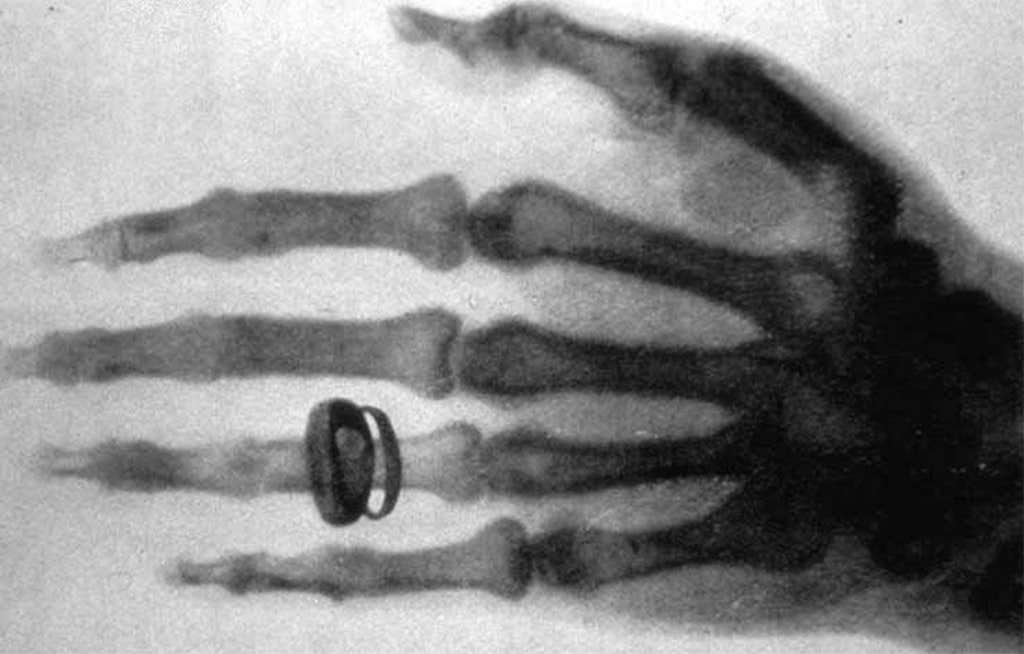

Wilhelm Röntgen/Old Moonraker/Wikimedia Commons.

Not long after his initial X-ray experiments, Röntgen learned that his rays could travel through human tissue to illuminate the bones within. He captured the bones in the hand of his wife, Anna Bertha Ludwig. “I have seen my death,” she said at the time. Röntgen noticed that the skin around her bones had a fainter shadow because it was more permeable to the rays

Lead image: Internet Archive Book Images / Wikimedia Commons